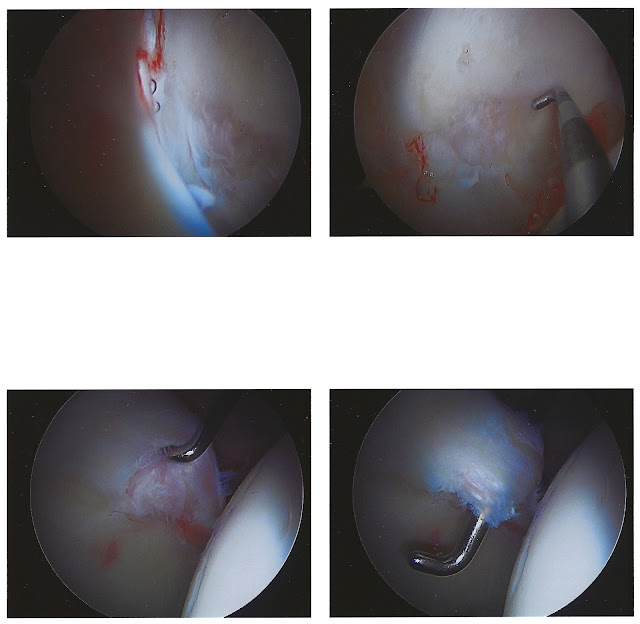

The long awaited arthroscope images from my hip-hoperation are finally posted!

The hipstergery was a success! I had a bone spur on the socket part (acetabulum) of the joint. They filed that down (debridement), which is why some of the surrounding area in the pictures look a little like shag carpeting. The spur was causing some minor impingement every time I moved my leg.

The cartilage tear was pretty large. It required 2 "anchors" to patch it down. I have 3 incision sites, one was for the camera and the 2 closest to each other were for the tools they used to complete the repair. I should get the stitches out on Friday... yes, Friday... the 13th...

| These are images taken on the way to the affected area. The contact lens in the bottom right image is just a bubble. |

| Image on bottom right shows the tear. It's so large, the probe fits all the way through it. |

| Here you can see the fuzzy areas of bone that they shaved down to get rid of the bone spur. |

| This shows them starting to tie down the flap of cartilage. It's funny how the rope looks like standard rope you can buy at the store. |

| The flap is tied down with 2 anchors and the spur is filed away. |